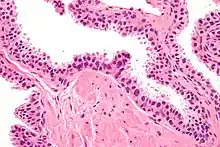

Micrograph showing high-grade prostatic intraepithelial neoplasia. H&E stain. | |

High-grade prostatic intraepithelial neoplasia (HGPIN) is an abnormality of prostatic glands and believed to precede the development of prostate adenocarcinoma (the most common form of prostate cancer).[1][2]

It may be referred to simply as prostatic intraepithelial neoplasia (PIN). It is considered to be a pre-malignancy, or carcinoma in situ, of the prostatic glands.

Histology

HGPIN typically has one of four different histologic patterns:[2]

- tufted (fascicular patterning)

- micropapillary,

- cribriform and,

- flat.

Its cytologic features are that of prostatic adenocarcinoma:

- presence of nucleoli,

- increased nuclear-to-cytoplasmic ratio and,

- increased nuclear size.

Microscopically, PIN is a collection of irregular, atypical epithelial cells. The architecture of the glands and ducts remains normal. The epithelial cells proliferate and crowding results in a pseudo-multilayer appearance. They remain fully contained within a prostate acinus (the berry-shaped termination of a gland, where the secretion is produced) or duct. The latter can be demonstrated with special staining techniques (immunohistochemistry for cytokeratins) to identify the basal cells forming the supporting layer of the acinus. In prostate cancer, the abnormal cells spread beyond the boundaries of the acinus and form clusters without basal cells. In HGPIN, the basal cell layer is disrupted but present. PIN is primarily found in the peripheral zone of the prostate (75-80%), rarely in the transition zone (10-15%) and very rarely in the central zone (5%), a distribution that parallels the zonal distribution for prostate carcinoma.[7]

Several architectural variants of PIN have been described, and many cases have multiple patterns. The main ones are tufting, micropapillary, cribriform, and flat. Although these different appearances may cause confusion with other conditions, they have not been found to be of clinical importance. Rarer types are signet-ring-cell, small-cell-neuroendocrine, mucinous, foamy, inverted, and with squamous differentiation.[3]